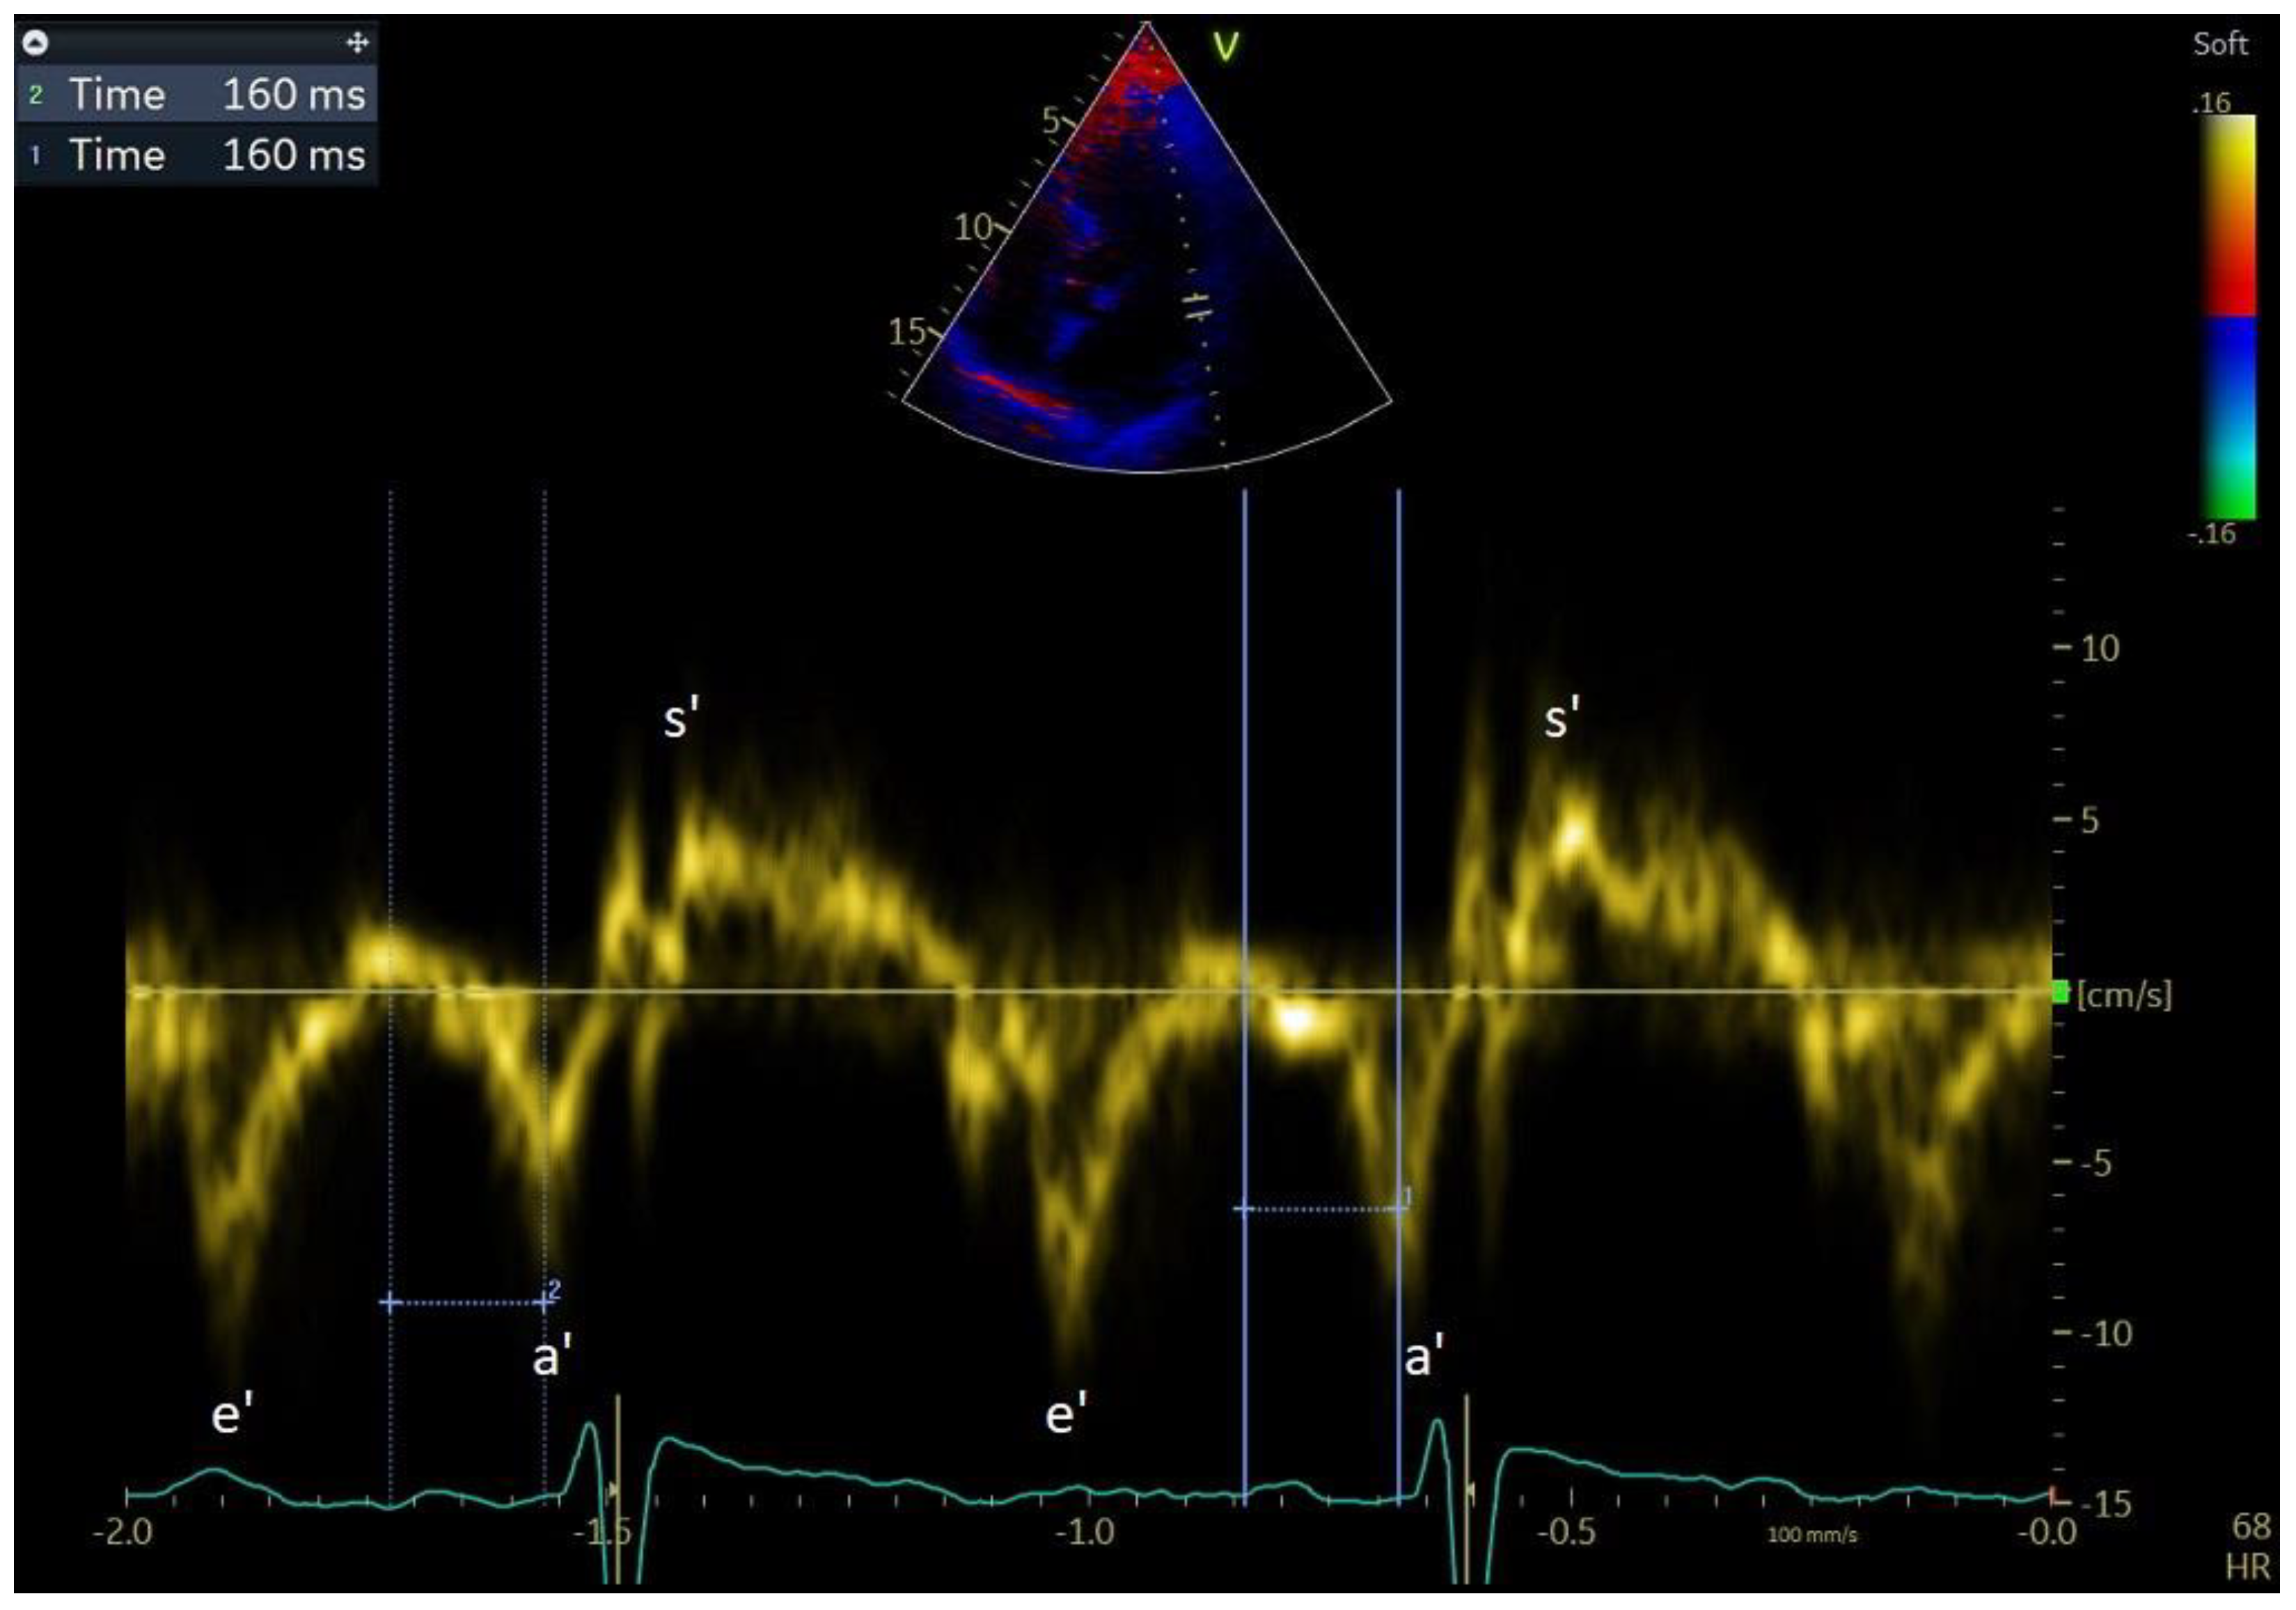

Recently, left and right atrial wall motion velocity was proven to possess prognostic value in terms of predicting the maintenance of the sinus rhythm after electrical cardioversion performed due to persistent AF, in which velocity measurements were performed directly using tissue Doppler imaging (TDI) (Figure 2) [46]. In this study, in a multivariate regression analysis including clinical and echocardiographic factors, only LAWMV was a significant predictor of SR maintenance over 12 months. Direct measurement, compared to the Q-analysis from colour Doppler imaging used by De Vos et al., has some advantages. Direct measurement is much less time-consuming and does not require additional software. Additionally, in Q-analysis, the sampling rate of the velocity measurement is affected by the size of the colour Doppler image that is recorded. Direct measurement of the left atrial wall motion velocity by means of tissue Doppler imaging is performed in the same way as a’ and e’ measurements of the velocity of diastolic motion of the mitral valve ring, but the Doppler gate should be located approximately 10 mm below the ring. A clear advantage of using colour Doppler imaging and the Q-analysis software is the ability to perform retrospective measurements from recordings made earlier.

Figure 2. Left atrial wall motion velocity (LAWMV). LAWMV 5 cm/s. Pulsed-wave tissue Doppler in the apical four-chamber projection during atrial fibrillation.